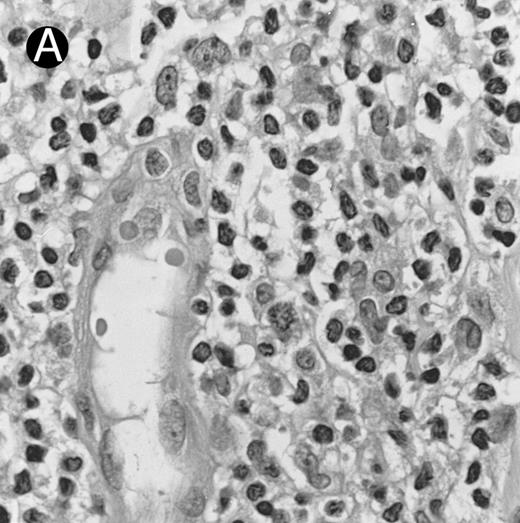

Nasal-type NK/T-cell lymphoma presenting as nodular skin lesion (case no. 28). (A) The skin shows focal necrosis of the epidermis and ulceration (arrow). (B) The lymphoid infiltrate in the dermis shows angiocentricity, as evidenced of the higher density of cells in the expanded walls of the blood vessels (arrows).

Histologically, the lymphomatous infiltrate was diffuse or patchy, with angiocentric and angiodestructive growth being observed in 30 cases (88.2%) (Figs 1 and 2). The cytologic composition was variable from case to case, including predominance of small cells, medium-sized cells, or large cells, or a mixture of these cell types (Fig 2 and 3). The tumor cell nuclei frequently showed irregular foldings and granular chromatin (Fig 2B). The larger cells possessed distinct nucleoli. The cytoplasm was moderate in amount and often pale. Karyorrhexis was usually prominent. Zonal tumor cell death, focal or confluent, was evident in 27 cases. In the 14 cases for which Giemsa-stained touch preparations were available, azurophilic granules could be identified in at least some of the neoplastic cells.